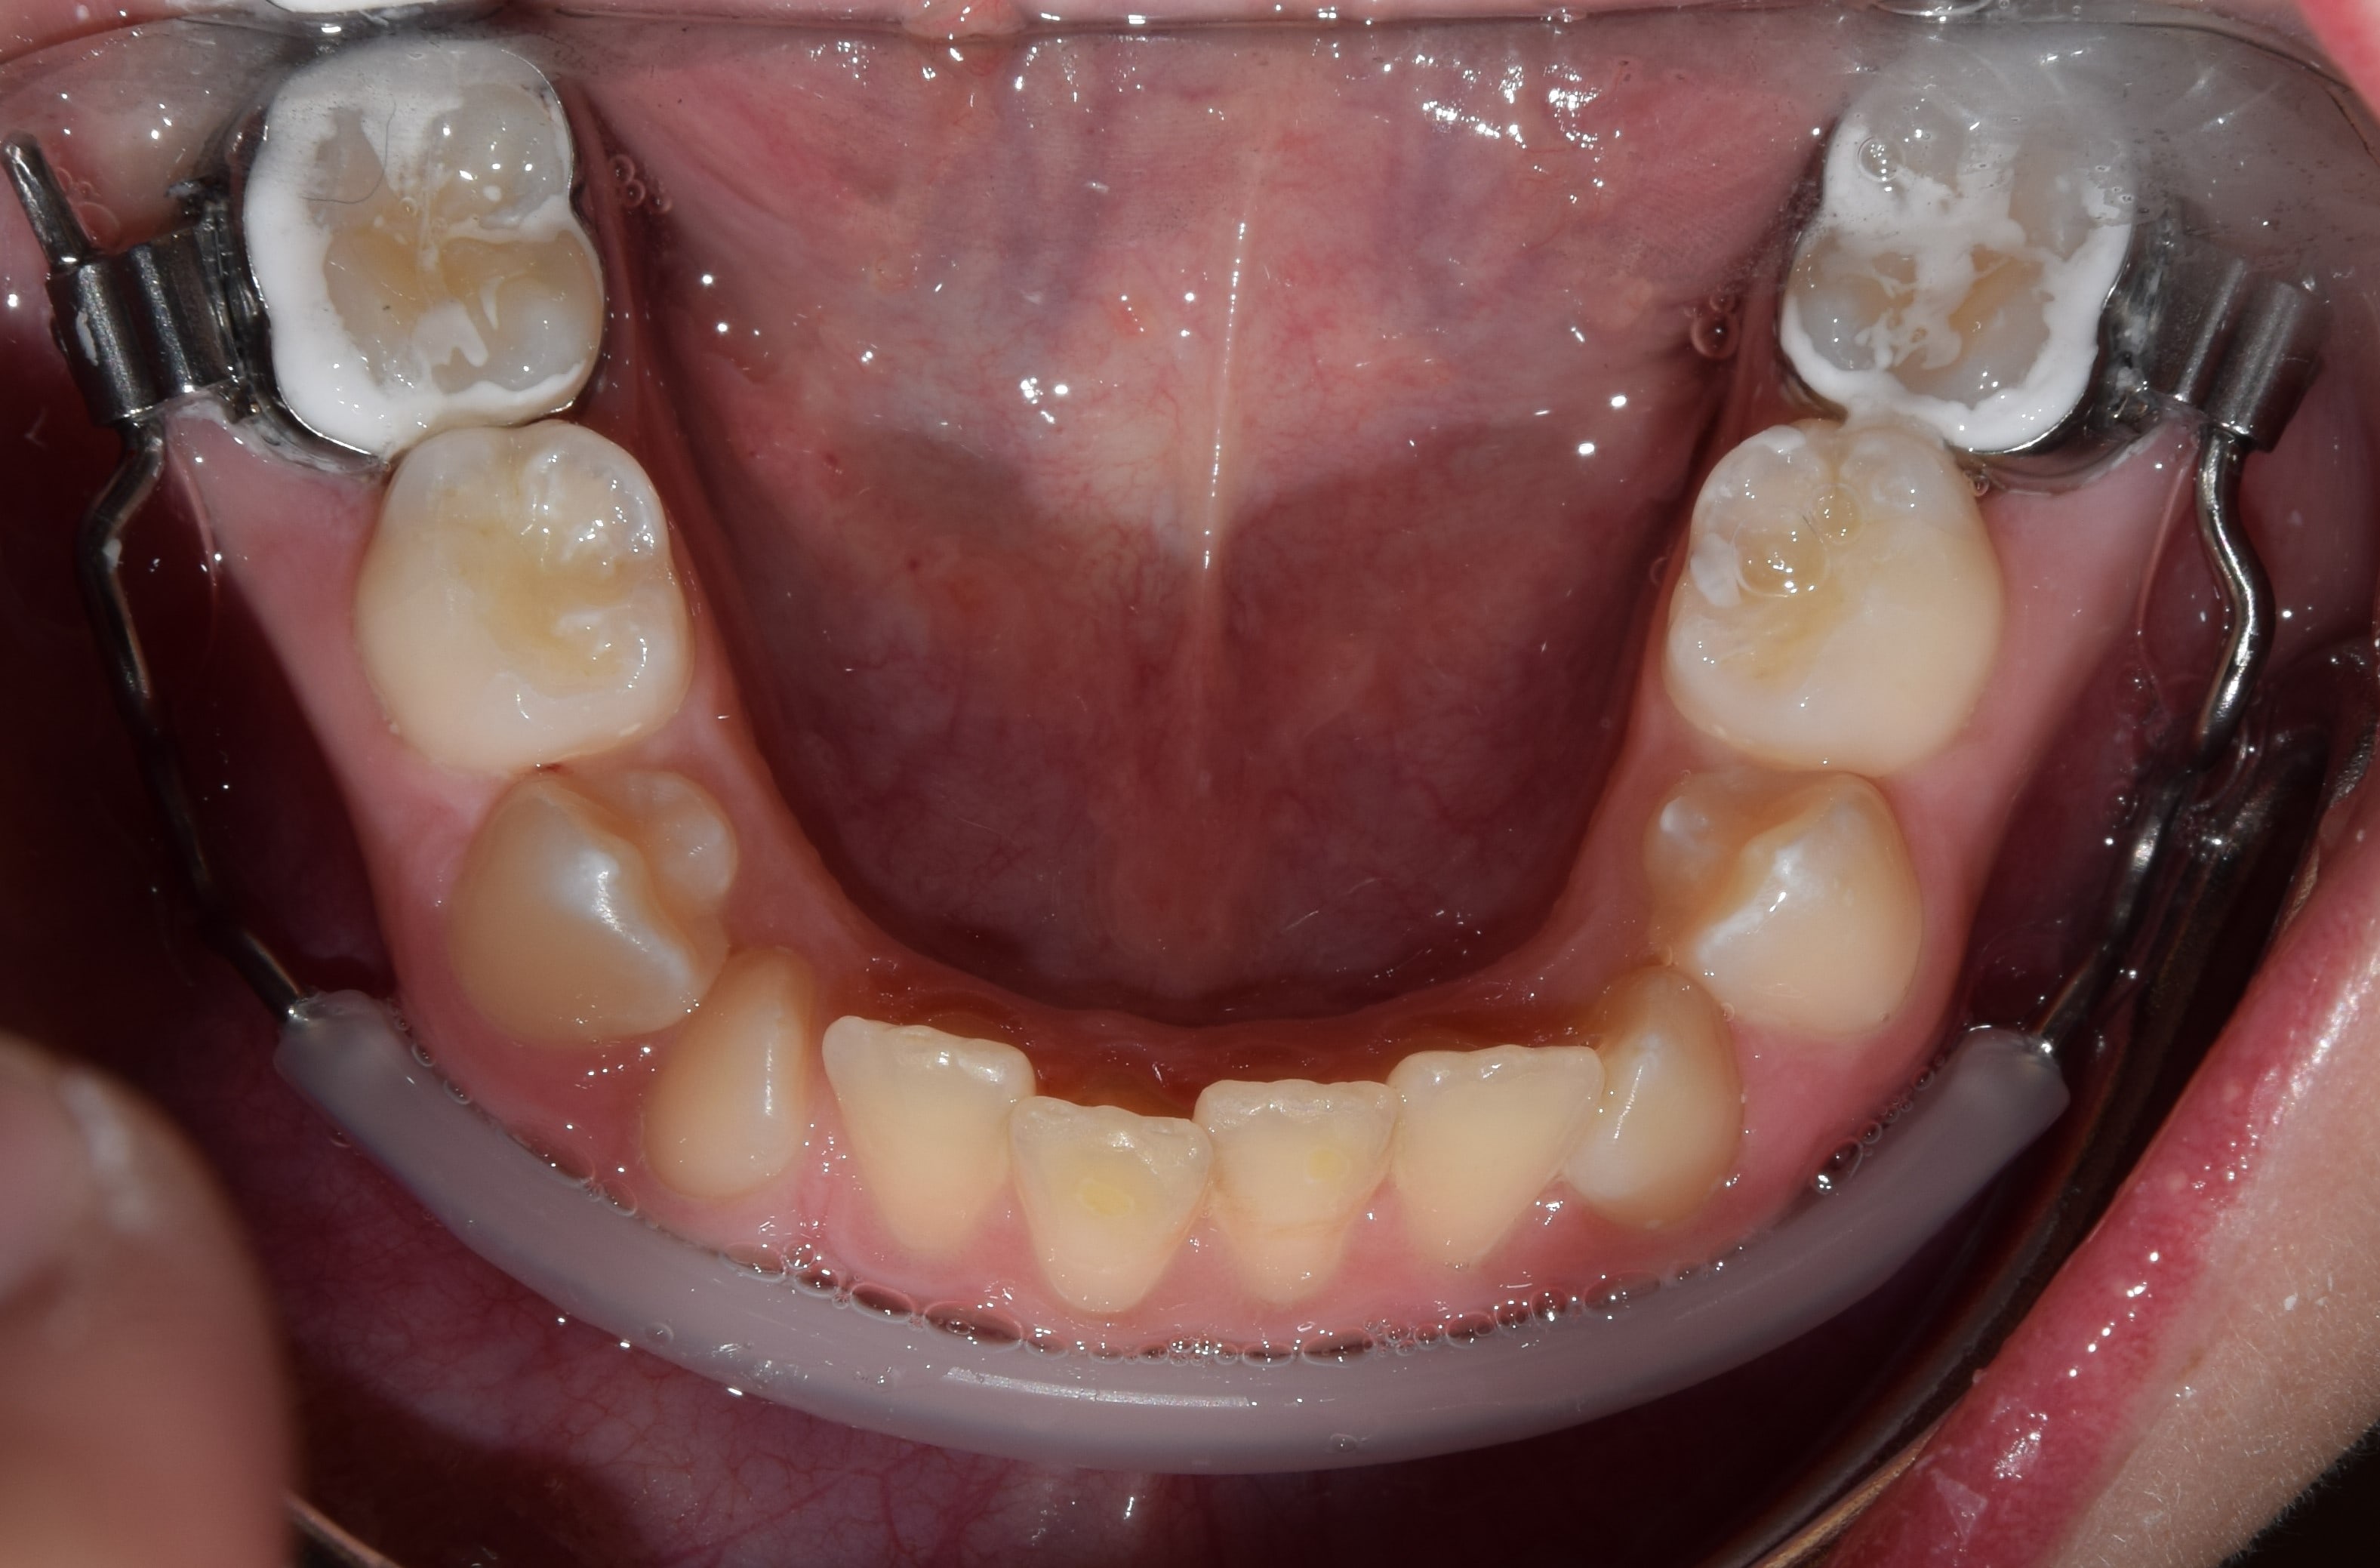

Korai vegyesfogazat

7-8 éves kor körül a gyermekek többségének korai vegyesfogazata van. Ez azt jelenti, hogy az első maradó nagyőrlők előtörtek, a tej metszőfogakat pedig felváltották a maradó metszőfogak.

Késői vegyesfogazat

10-11 éves korban beszélünk késői vegyesfogazatról, amikor megkezdődik az oldalsó tejfogak elvesztése, és a tej őrlők, tejszemfogak helyére nőnek a maradó kisőrlők és szemfogak. Késői vegyesfogazatban a szájüregben eltérő sorrendben nőnek a maradófogak, illetve esnek ki a tejfogak.

Torlódott fogazat

A legtöbbször panaszt okozó fogszabályozási kórkép. Számos oka lehet a fogtorlódások kialakulásának. Előfordulhat, hogy a fogak mérete jóval nagyobb, mint az állcsontok által biztosított hely. Bizonyos esetekben a fogak nyelv felé való dőlése miatt szűkül be a fogív, és emiatt a szűkebb íven csak torlódva férnek el a fogak. Fontos a torlódás okának pontos feltárása, hiszen sikeres kezelést csak így végezhetünk.

A D-gainer készülék tulajdonképpen egy részleges rögzített fogszabályzóként fogható fel, melyet elsősorban gyerekeknél, korai vagy késői vegyesfogazatban alkalmazunk. Szintén önligírozó bracketeket használok a D-gaineres kezeléseknél. A rendszert a felső első nagyőrlők, és a négy felső metszőfog alkotja, melyeket ugyanúgy fogszabályzó ívvel kötünk össze., mint a teljes rögzített fogszabályzónál. A nagyőrlők és a metszőfogak közé az ívre egy hosszú tolórugót helyezek. A D-gainerrel jelentős mértékű helyet lehet teremteni a felső fogívben, illetve nagyfokú oldalirányú tágítás végezhető. Alkalmas az előrehelyezett felső nagyőrlők hátravitelére, főként hátraforgatására. Tipikus indikációja, ha a felső állcsontban nincs elegendő hely a szemfogaknak.